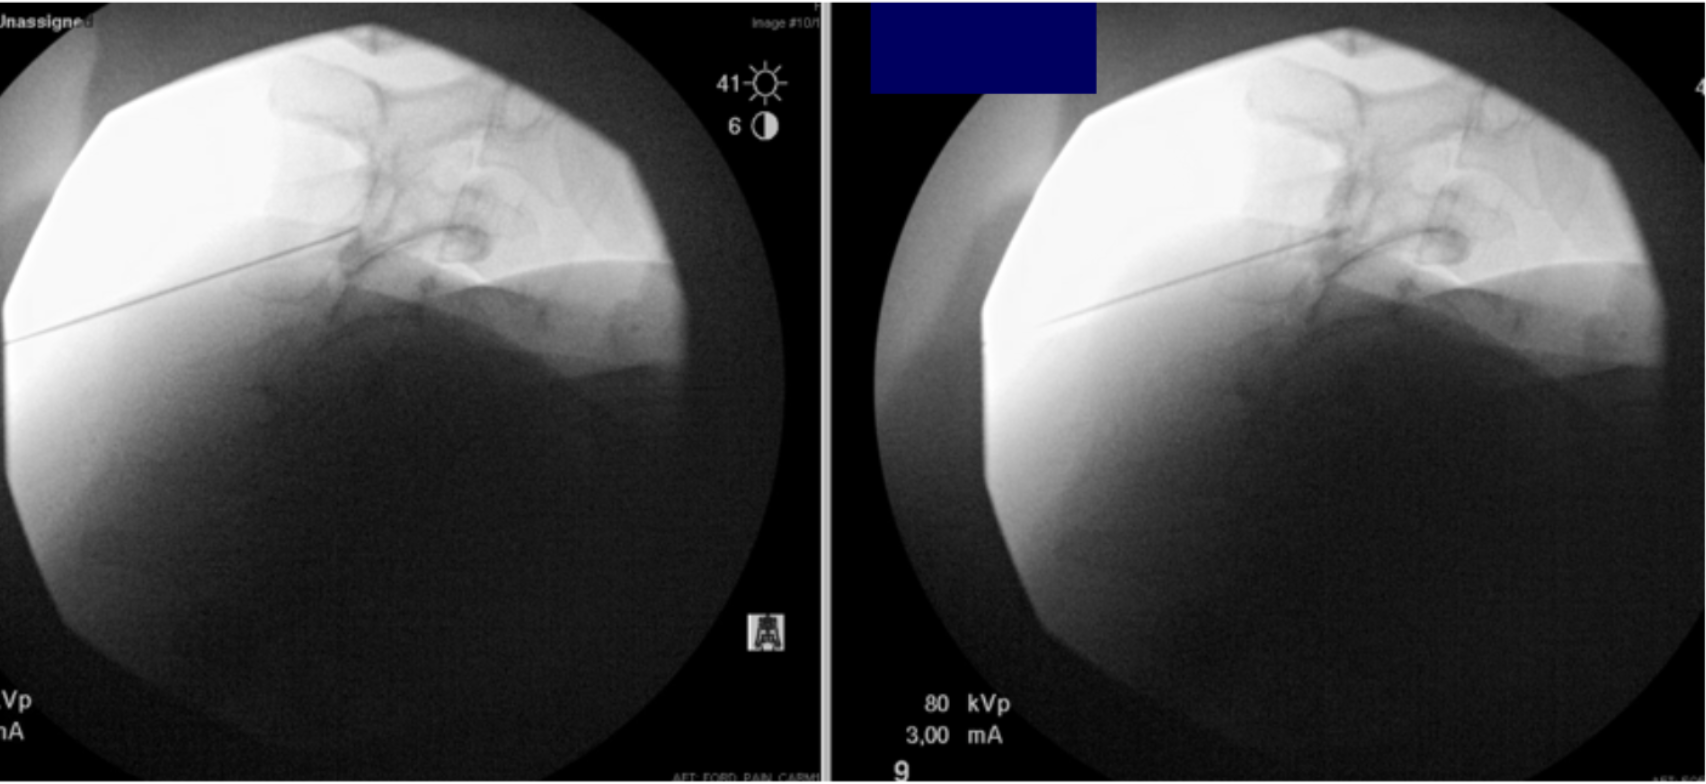

Pseudo-Subarachnoid Hemorrhage Following Cervical Medial Branch Block Using Gadolinium-Based Contrast: A Case Report and Review of the Literature

This case report explores the evidence behind recognizing and treating conditions caused by gadolinium-based contrast agents — including pseudo-subarachnoid hemorrhage.